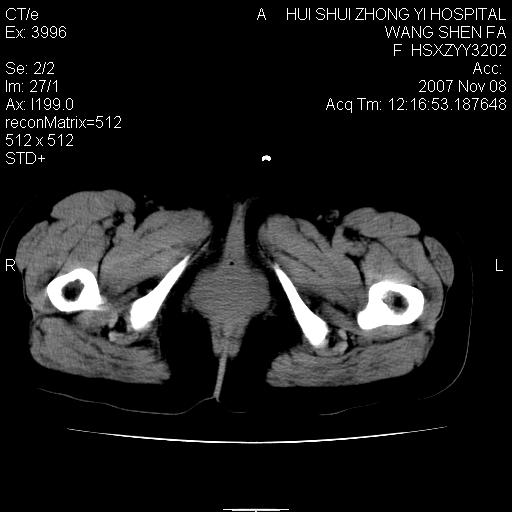

标题: CT10389:女,38岁,腹部巨大包块 [打印本页]

腹部巨大包块半年,质硬,边界不清。

腹腔及盆腔内可见巨大软组织肿物影,内部密度欠均匀,边界尚清晰,周围组织受压移位明显,右侧输尿管受压明显,上端扩张肾盂轻度积水,病灶外形分叶明显,似多个肿物融合而成。考虑来源于间叶组织的恶性肿瘤可能性大

下腹部巨大软组织影,密度不均匀,并可见分隔,病灶边缘较清,肠管受压移位。子宫未显示。盆腔、双侧腹股沟未见明显肿大淋巴结。考虑:1.卵巢病变可能性大,囊腺癌>卵巢癌>囊腺瘤.2.多发性阔韧带子宫肌瘤待除外.

腹腔及盆腔内可见巨大软组织肿物影,内部密度欠均匀,边界尚清晰,周围组织受压移位明显,膀胱前上移位,右侧输尿管受压明显,上端扩张肾盂轻度积水。考虑:1卵巢病变可能性大,囊腺癌>卵巢癌>囊腺瘤.2 子宫病变,子宫肌瘤?

盆腔及下腹部多发肿块,密度不均,与子宫关系密切,周围肠管受压改变,盆腔内未见肿大淋巴结,考虑多发性巨大子宫肌瘤可能。直接手术吧!

下腹部巨大软组织影,密度不均匀,并可见分隔,病灶边缘较清,肠管受压移位。病灶下部与子宫及附件关系密切。盆腔、双侧腹股沟未见明显肿大淋巴结。考虑:1.卵巢实质性肿瘤可能性大,卵巢癌>颗粒细胞>卵泡膜细胞瘤>纤维瘤.2.多发子宫肌瘤待除外.

膀胱向前明显的推压移位,子宫增大明显,肠管推压移位,未见明显的侵润;患者女性,育龄期,考虑多发子宫肌瘤可能性大